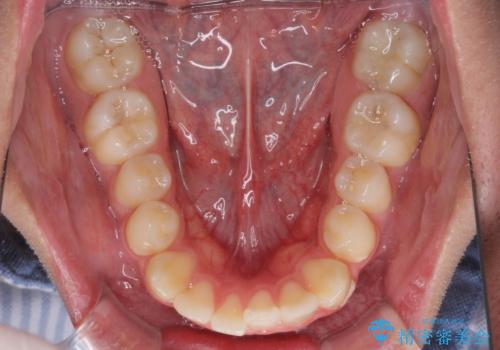

- 前歯のデコボコと口元の突出感を気にして来院された患者様です。

上下前歯がくちばしのように突出していたため、上下左右の第一小臼歯4本を抜歯し、ワイヤー装置にて矯正治療を行うこととしました。

上顎骨に対して下顎骨がやや前方位に位置しているため、下顎前歯をあまり内側に移動させることができず、口元の突出感改善は期待以上にはならないと予測しておりましたが、満足いくの引っ込み具合となりました。